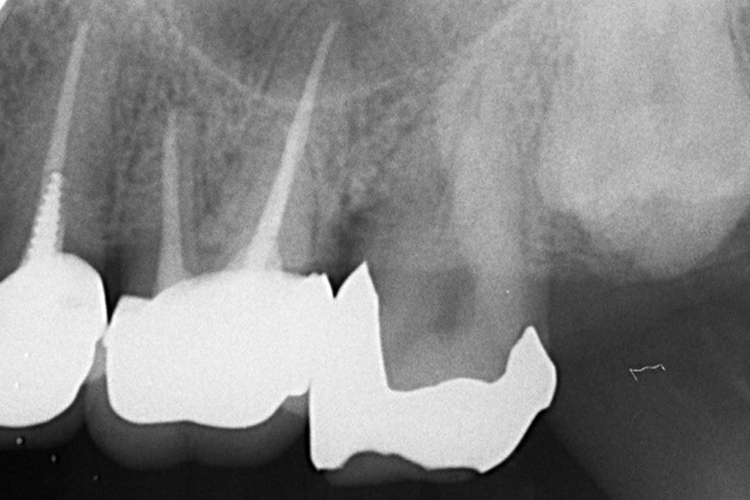

実際の実施例2

この患者様は、スケーリングより歯周ポケットが6mm以上ある患者様で患者様ご本人も歯周病になりかけている自覚がありました。また、口臭も気になされていましたので、ブルーラジカルの適用症例と判断し、施術を行いました。

(実施前)

施術前のレントゲンと口腔内写真です。施術前にプラークの除去を行ってから、施術します。